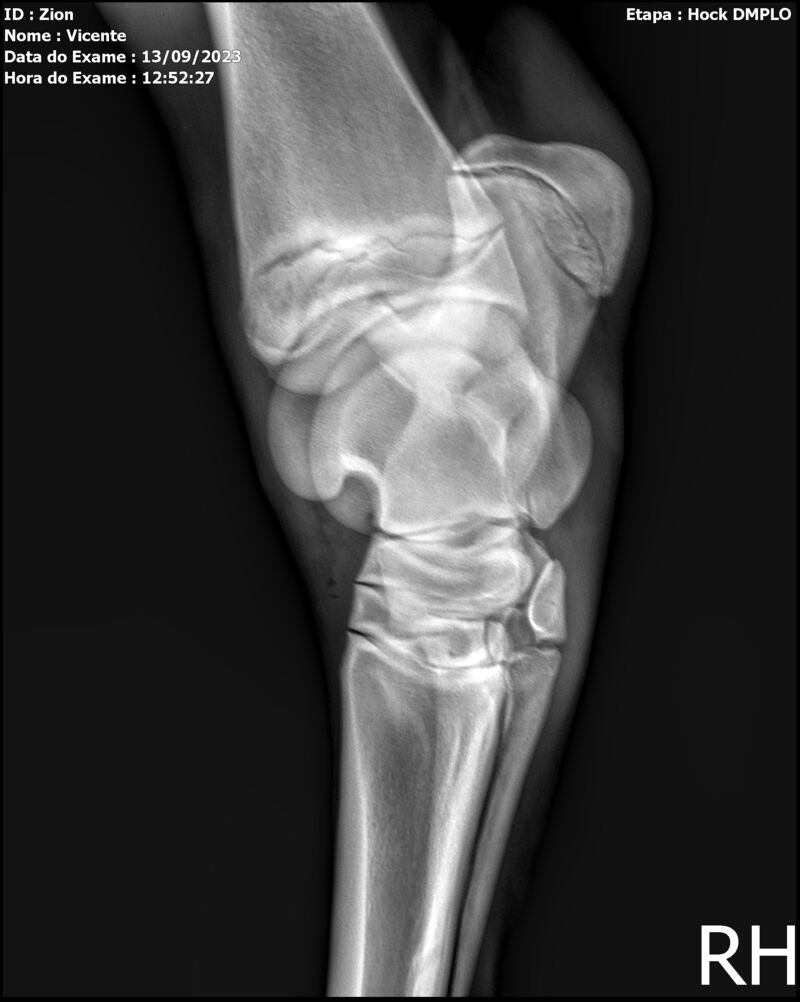

ZION ZC

Raça: BRASILEIRO DE HIPISMO

Sexo: MACHO - POTRO

Nascimento: 17/12/2022

Altura Aproximada: 1,51

Pel.: CASTANHO

Registro: EM AND

Vend.: VICENTE CONTE

Local : PORTO FELIZ/SP